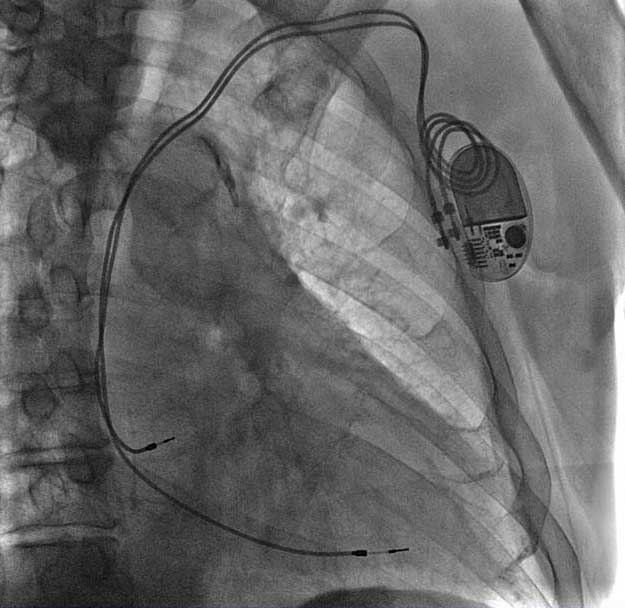

ENDURITY MRI™ 雙腔起搏器術後DSA影像